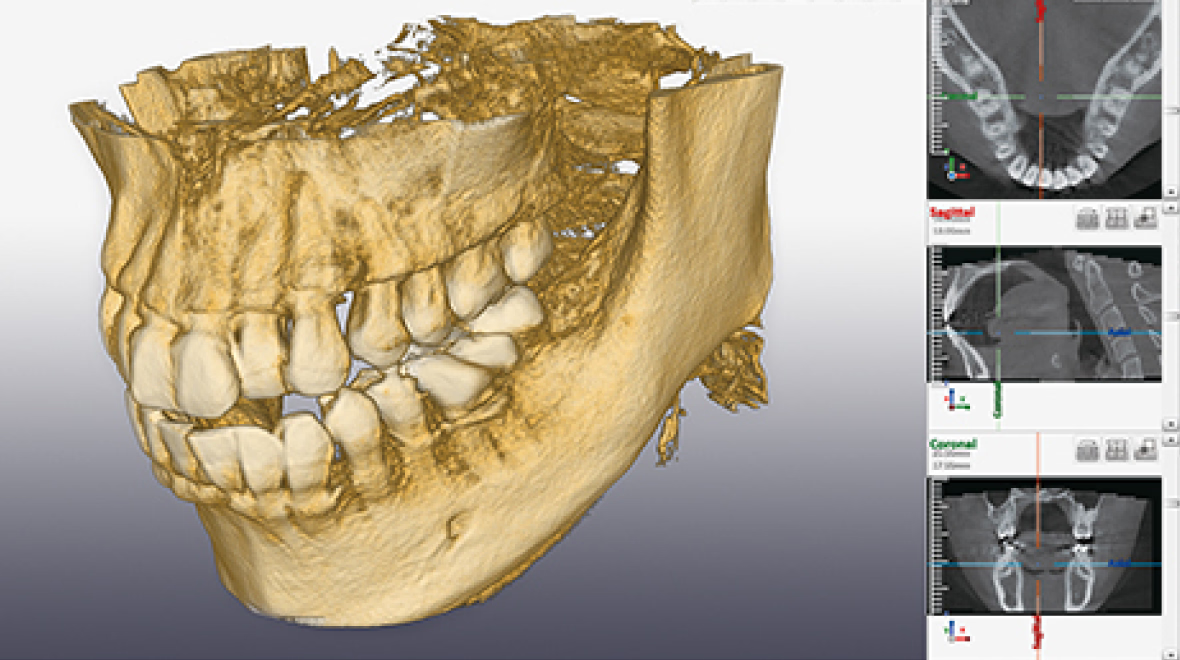

歯科用CT(CBCT)

歯科用CT(CBCT)は、従来のレントゲン(X線撮影)では把握しきれなかった骨や歯の形状・神経の位置を、立体的な3D画像で確認できる機器です。

インプラント治療、根管治療、歯周病治療など、精密な診断が必要なあらゆるシーンで活躍します。

また、被ばく線量も大幅に低減されており、安全性にも配慮されています。

歯科用CT(CBCT)とレントゲン

(X線撮影)の違い

| 歯科用CT(CBCT) | レントゲン(X線撮影) | |

|---|---|---|

| 画像 | 3Dで見れる | 2Dで見れる |

| 特徴 | 骨の厚み・高さ、神経や血管の位置まで詳細に確認 | 骨や歯の全体像は把握できるが、厚みや奥行きは分かりにくい |

| 診断の正確さ | 限界あり | 標準的 |

| 被ばく線量 | 手軽・広範囲が見える | より少ない |

| 保険適用 | 自由診療 | 保険適用 |

また体の構造上、皮質骨(骨の表面を構成する硬くて緻密な骨)の吸収を伴わないと透過像が認識できない等の欠点があり、病気を見逃してしまう可能性もあります。

一方で、歯科用CTでは歯の細かな構造を立体的な3D画像で確認でき、精密な診断が必要な場面で大きな力を発揮します。

当クリニックで導入している歯科用CT

通常のレントゲンは国内の歯科医院で約95%も普及しているのに対し、歯科用CTは全国の歯科医院のうち約10~15%程度でしか導入が進んでいません。

(※2023年時点)

また、当クリニック院長は2013年に日本顕微鏡歯科学会認定医を取得しております。